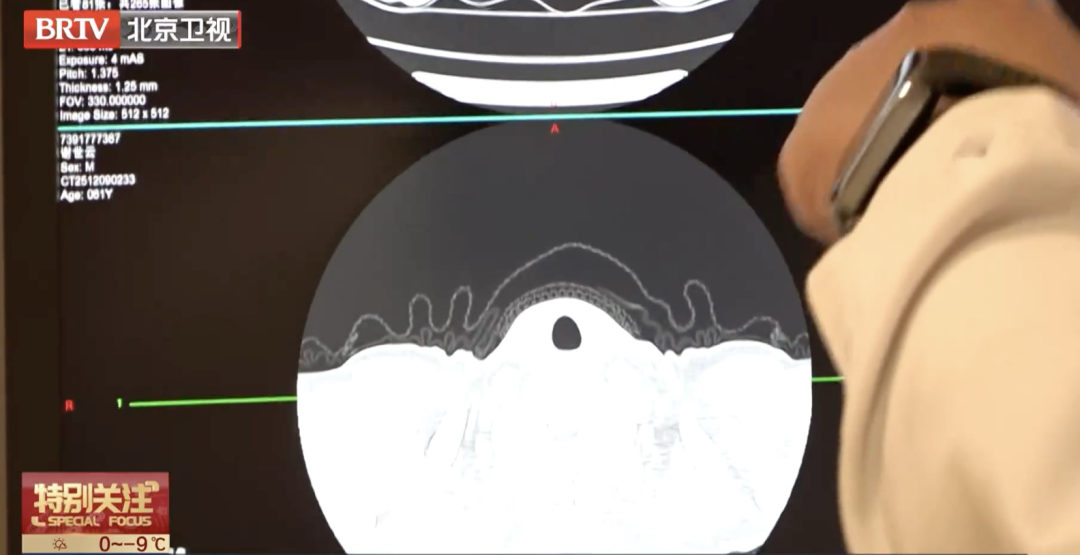

北京胸科医院医学影像科主任侯代伦介绍了“肺小结节AI辅助诊断系统”的使用方法:一个患者出来了这么多图像,先看肺窗,还要看纵隔窗里的血管情况,加起来就有600多幅图像,人工阅片需要几分钟到几十分钟不等,到这个人工智能软件点运算以后,这里(显示)肺部肺结节11个,淋巴结0个,都已经判读完了,自动测量3.8mm*3.1mm,恶性概率35%。

此次升级后,该系统对肺结节的诊断能力进一步增强,特别是对与血管或胸膜紧密相连,过去容易漏判的结节,识别更为准确。同时,新系统经过大量数据训练,提高了结节良恶性判断的准确性。